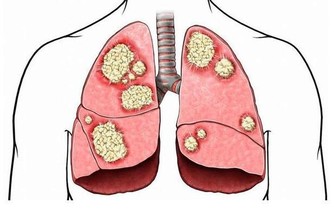

一開始,我們的大腦能以加快信息處理速度的方式來適應這種壓力。它會本能地向腎上腺發出分泌皮質醇和腎上腺素的信號。短期看,這些應激激素可以提高能量水平並增強記憶力,但隨著時間推移,它們對大腦的傷害很大。實驗證明,壓力下的動物在海馬回(hippocampus)的記憶細胞比正常狀態下小得多。

海馬回呈馬蹄形,分佈在大腦顳葉內側,管理人對新信息的學習和記憶。但是,當我們進行“多任務處理”時,一旦大腦負載過重,它的信息處理區域會從海馬回(負責記憶)轉移到紋狀體(負責機械性任務),從而導致理解困難,甚至一旦完成任務就忘得一乾二淨。